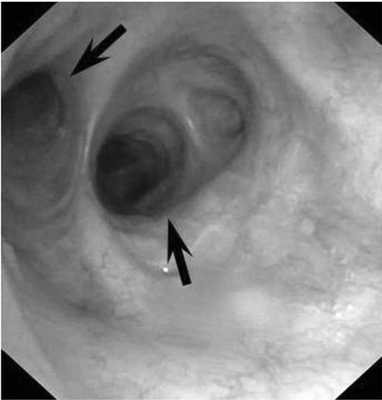

Рис. 3. Формирующийся стеноз промежуточного бронха. Рубцовое сужение диаметром 4 мм, протяженностью 5-6 мм (указано стрелкой).

Рис. 4. Состояние после стентирования промежуточного бронха. В просвете промежуточного бронха определяется самофиксирующийся стент ЭПТС 9 ×15. Произведено моделирование стента для обеспечения адекватной вентиляции средней доли и 6-го сегмента нижней доли правого легкого (указано стрелкой).

Через 86 сут после травмы пациент обратился в институт с жалобами на затрудненное дыхание, кашель с мокротой и примесью крови. При рентгенографическом исследовании патологических изменений не выявлено. Была выполнена ФБС, при которой выявлена проксимальная дислокация стента в просвет левого главного бронха (рис. 5). Стент был удален. Просвет промежуточного бронха резко сужен до 2-3 мм в диаметре за счет рубцово-грануляционной ткани (рис. 6). Проксимальный край сужения расположен на 20 мм дистальнее карины, протяженность сужения составила 15 мм. В экстренном порядке выполнена ригидная бронхоскопия с реканализацией и рестентированием просвета промежуточного бронха самофиксирующимся стентом ЭПТС - 9×15 длиной 3 см. Раскрытие стента полное. Проксимальный край стента располагался на уровне нижнего края устья верхнедолевого бронха правого легкого, а дистальный край - на уровне верхнего края устья среднедолевого бронха. Проходимость среднедолевого бронха и всех сегментарных бронхов нижней доли сохранена. На 4-е сутки после восстановления просвета и рестентирования промежуточного бронха пациенту выполнена контрольная ФБС, при которой отмечено удовлетворительное положение стента, однако на выдохе определяли пролабирование грануляции из-под дистального края стента с частичным перекрытием устья среднедолевого бронха. С помощью электрокоагуляции грануляция удалена, проходимость среднедолевого бронха восстановлена. При контрольной ФБС на 6-е сутки положение стента удовлетворительное, проходимость бронхов средней и нижней доли правого легкого сохранена. Пациент выписан в удовлетворительном состоянии на 7-е сутки после рестентирования.